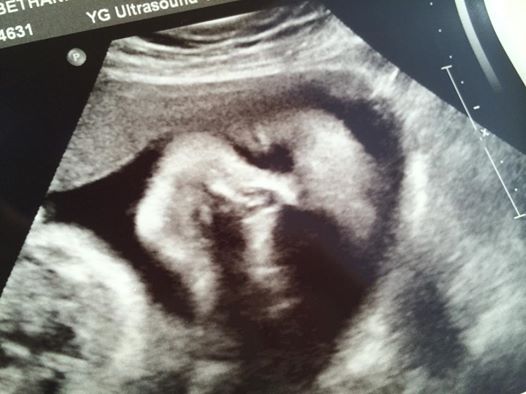

29 Weeks Pregnant Ultrasound

29 Weeks Pregnant Ultrasound. Your baby's skeleton is hardening. Wondering how many months along you are at 29 weeks pregnant?.

At 29 weeks pregnant, baby is about the size of a fanny pack. However, your next check up appointment may by at week 30. During the 29 weeks ultrasound you can see that your baby is getting crammed in there due to its rapid growth.

To help you count your baby's kicks, download our fetal movement tracker. If you were to look at a 29 weeks pregnant ultrasound, you may see that baby’s growing white fat deposits under the skin, and his or her energy is surging because of it!. By week 29 of pregnancy, your tummy is probably large enough that you can't see your legs when you're standing anymore.

The average 29-week fetus weighs about 2.5 lbs. 29 Weeks Pregnant Ultrasound. Pregnancy Weeks is the ultimate pregnancy website where you can find best information about pregnancy stages week by week.

Normal 29-week pregnancy symptoms!. Your baby's brain is busy developing billions of neurons. If you take a look at a 29 weeks pregnant ultrasound, you will be able to see that the baby is growing white fat deposits under the skin.